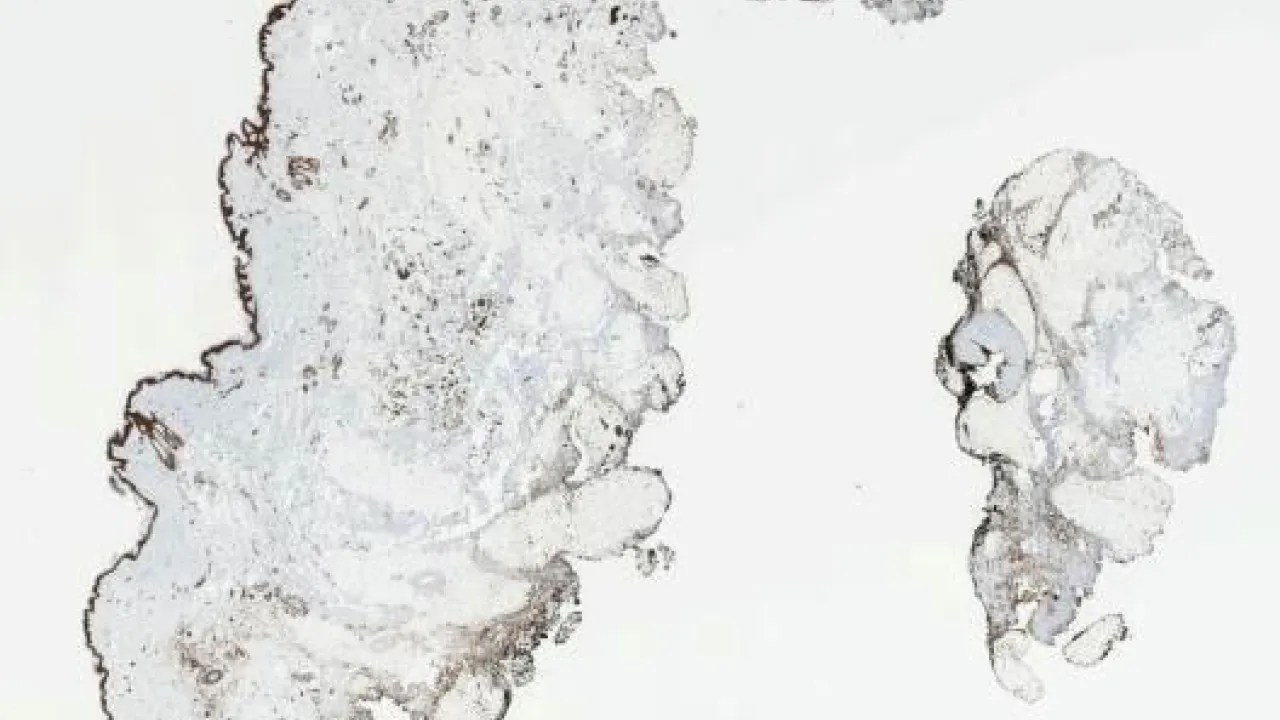

Skin, Involuting infantile hemangioma, GLUT1 stain